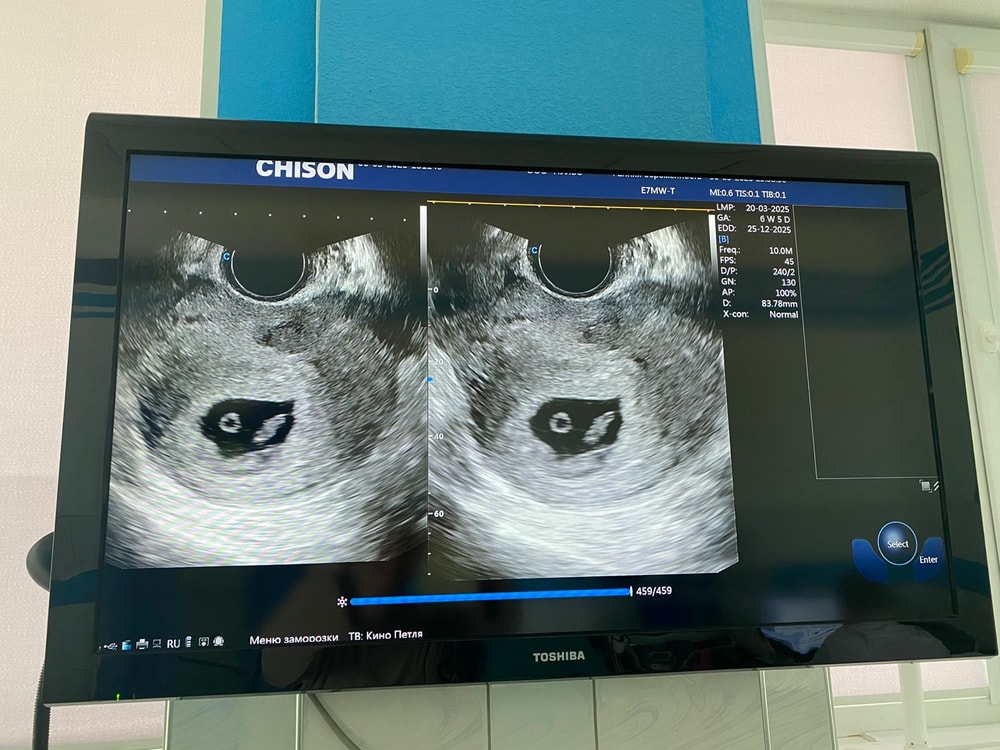

Метод Рамзи,предположите?